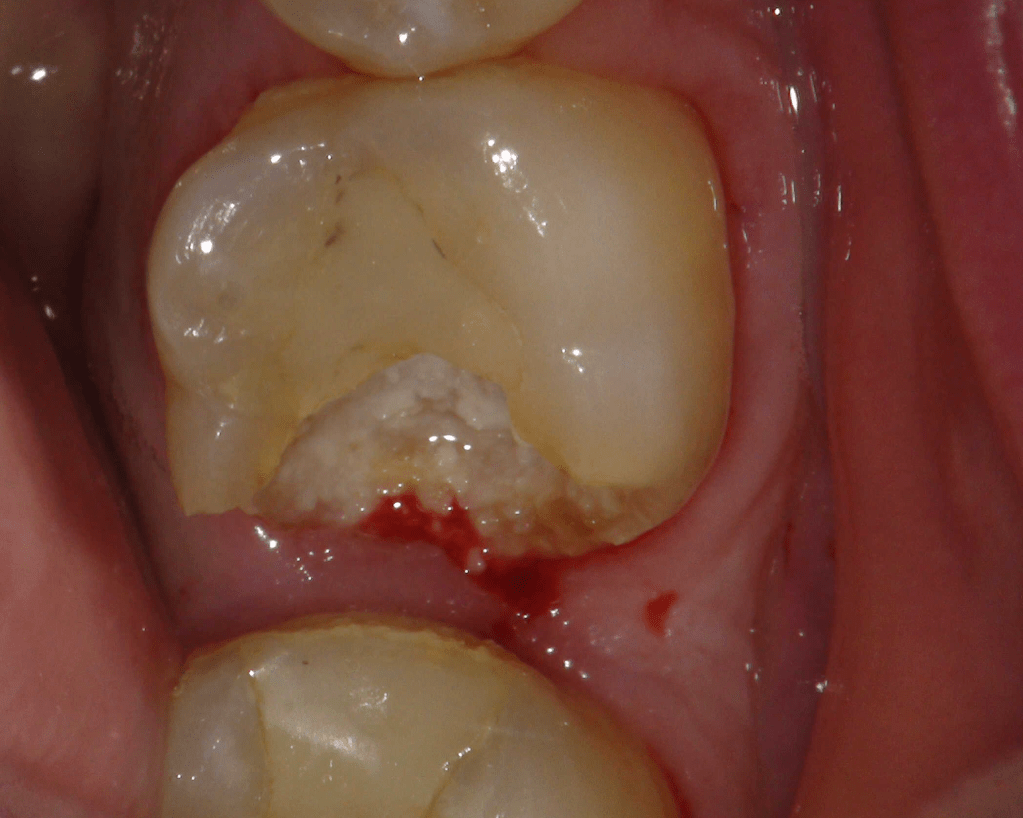

Reconstrucción preendodóntica

Reco pre-endo, molar inferior

Reco preendo + 4 conductos molar superior